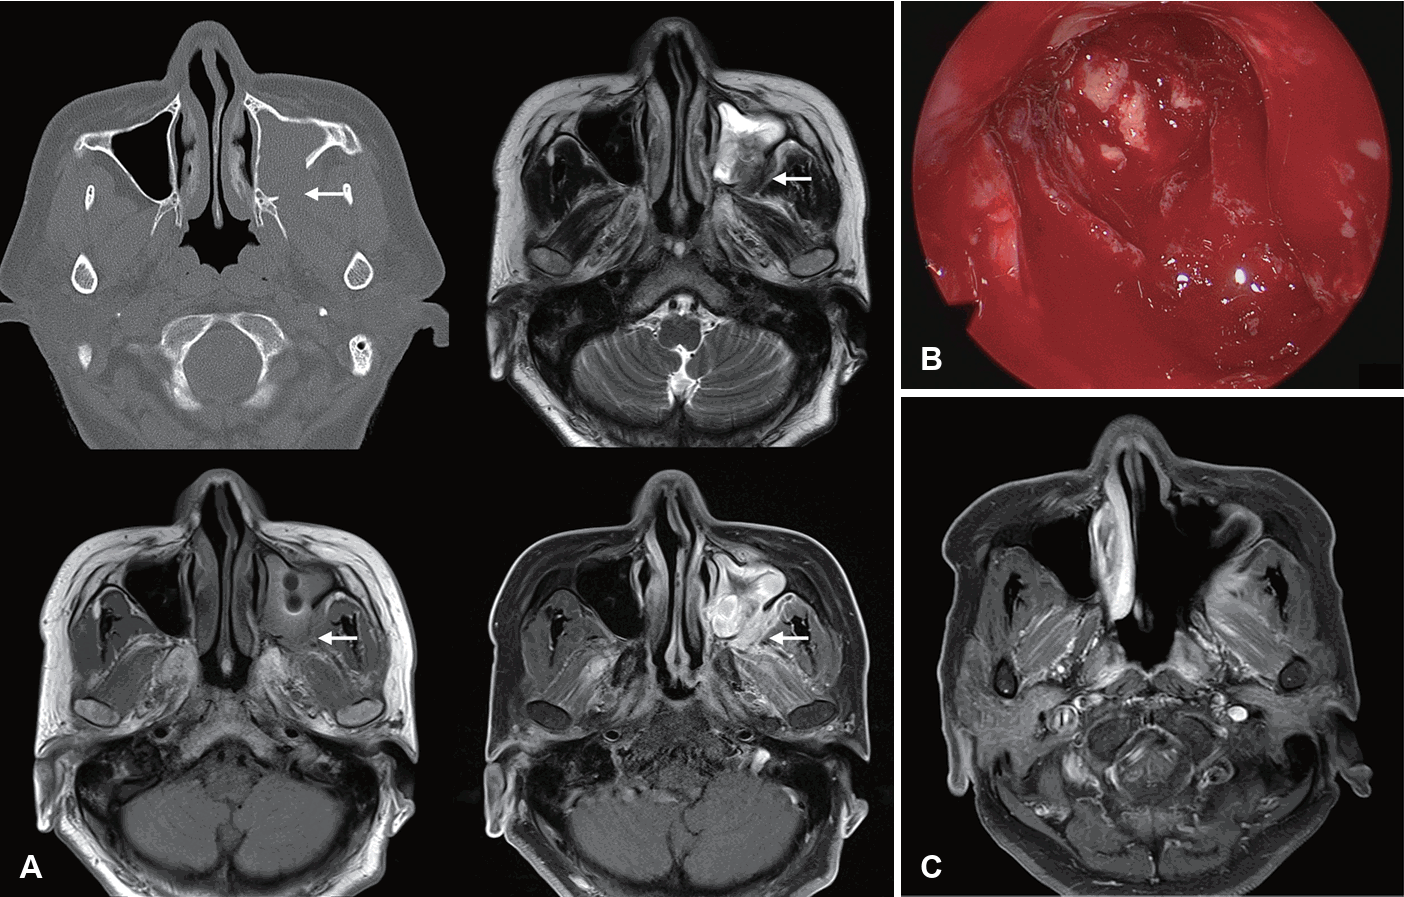

Endoscopic findings

Nasal endoscopy is commonly used to evaluate suspected AIFRS patients by directly visualizing the nasal cavity. Key findings suggestive of AIFRS include mucosal edema, crusting, friability, tissue discoloration (pallor or darkening), ulceration, necrosis, and lack of sensation (Fig. 1). Although the procedure exhibits high specificity for detecting abnormalities, its sensitivity ranges considerably from 49% to 75% [19,23,38,41,42], indicating that negative findings cannot reliably rule out the disease.

Endoscopic findings of acute invasive fungal sinusitis. A: Crusting and pale mucosa of the nasal cavity. B: Necrotic mucosa of the nasal cavity and hard palate. C: Classic black middle turbinate.

Limited research exists on the routine use of endoscopy [43]. Major limitations include the inability to visualize paranasal sinuses in non-operated patients, post-surgical debris interference, and patient intolerance. Endoscopic changes may indicate late-stage disease. Despite these limitations, nasal endoscopy remains valuable due to its low cost, minimal time investment, and high specificity for identifying lesions. While nasal endoscopy has limited sensitivity as a screening tool, reducing its effectiveness for early AIFRS detection, it should be performed in immunocompromised patients if IFRS is suspected to identify mucosal abnormalities.